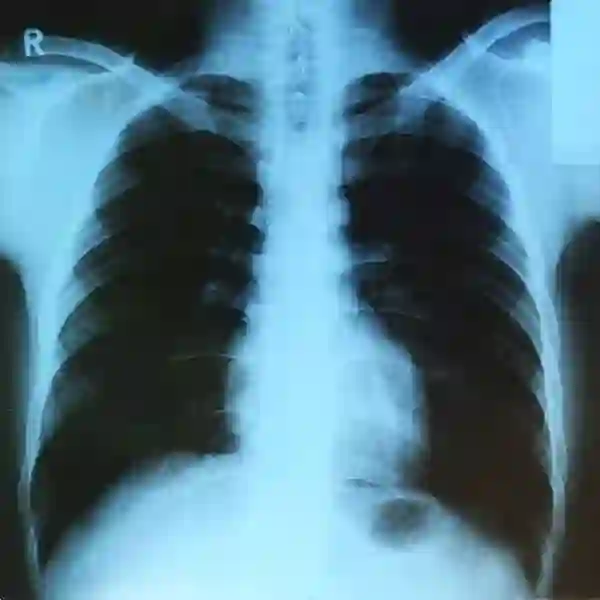

X线检查很常用,如体检拍胸片或摔倒后排除骨折时都会用到。其影响取决于胎龄和射线剂量。

单次X线检查一般不会伤害胎儿,但多次高剂量的检查可能导致胚胎死亡、先天畸形、生长受限及智力缺陷等。

人体肺部的X射线 | Wikimedia Commons